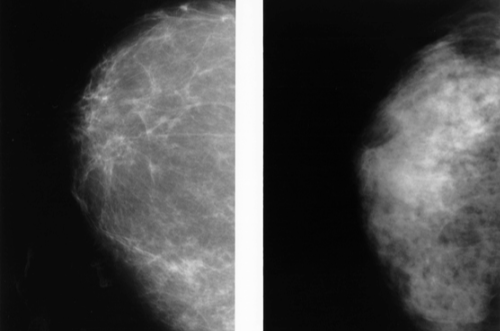

유방 촬영술(Mammography)

기본 유방 검진 검사로 유방 촬영 X-ray입니다.

유방조영상 촬영 중에 유방을 두 개의 판 사이에 압박한 다음 X-ray를 촬영합니다.

검사 중 통증이 상당할 수도 있습니다.